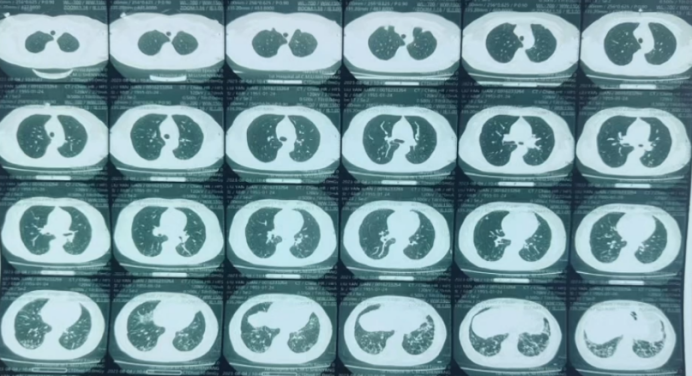

2023年11月10日HRCT:双肺间质性炎症较前(11月6日)略加重,双侧胸腔积液(图4)

图片

4  复查胸部CT(2023-11-10)